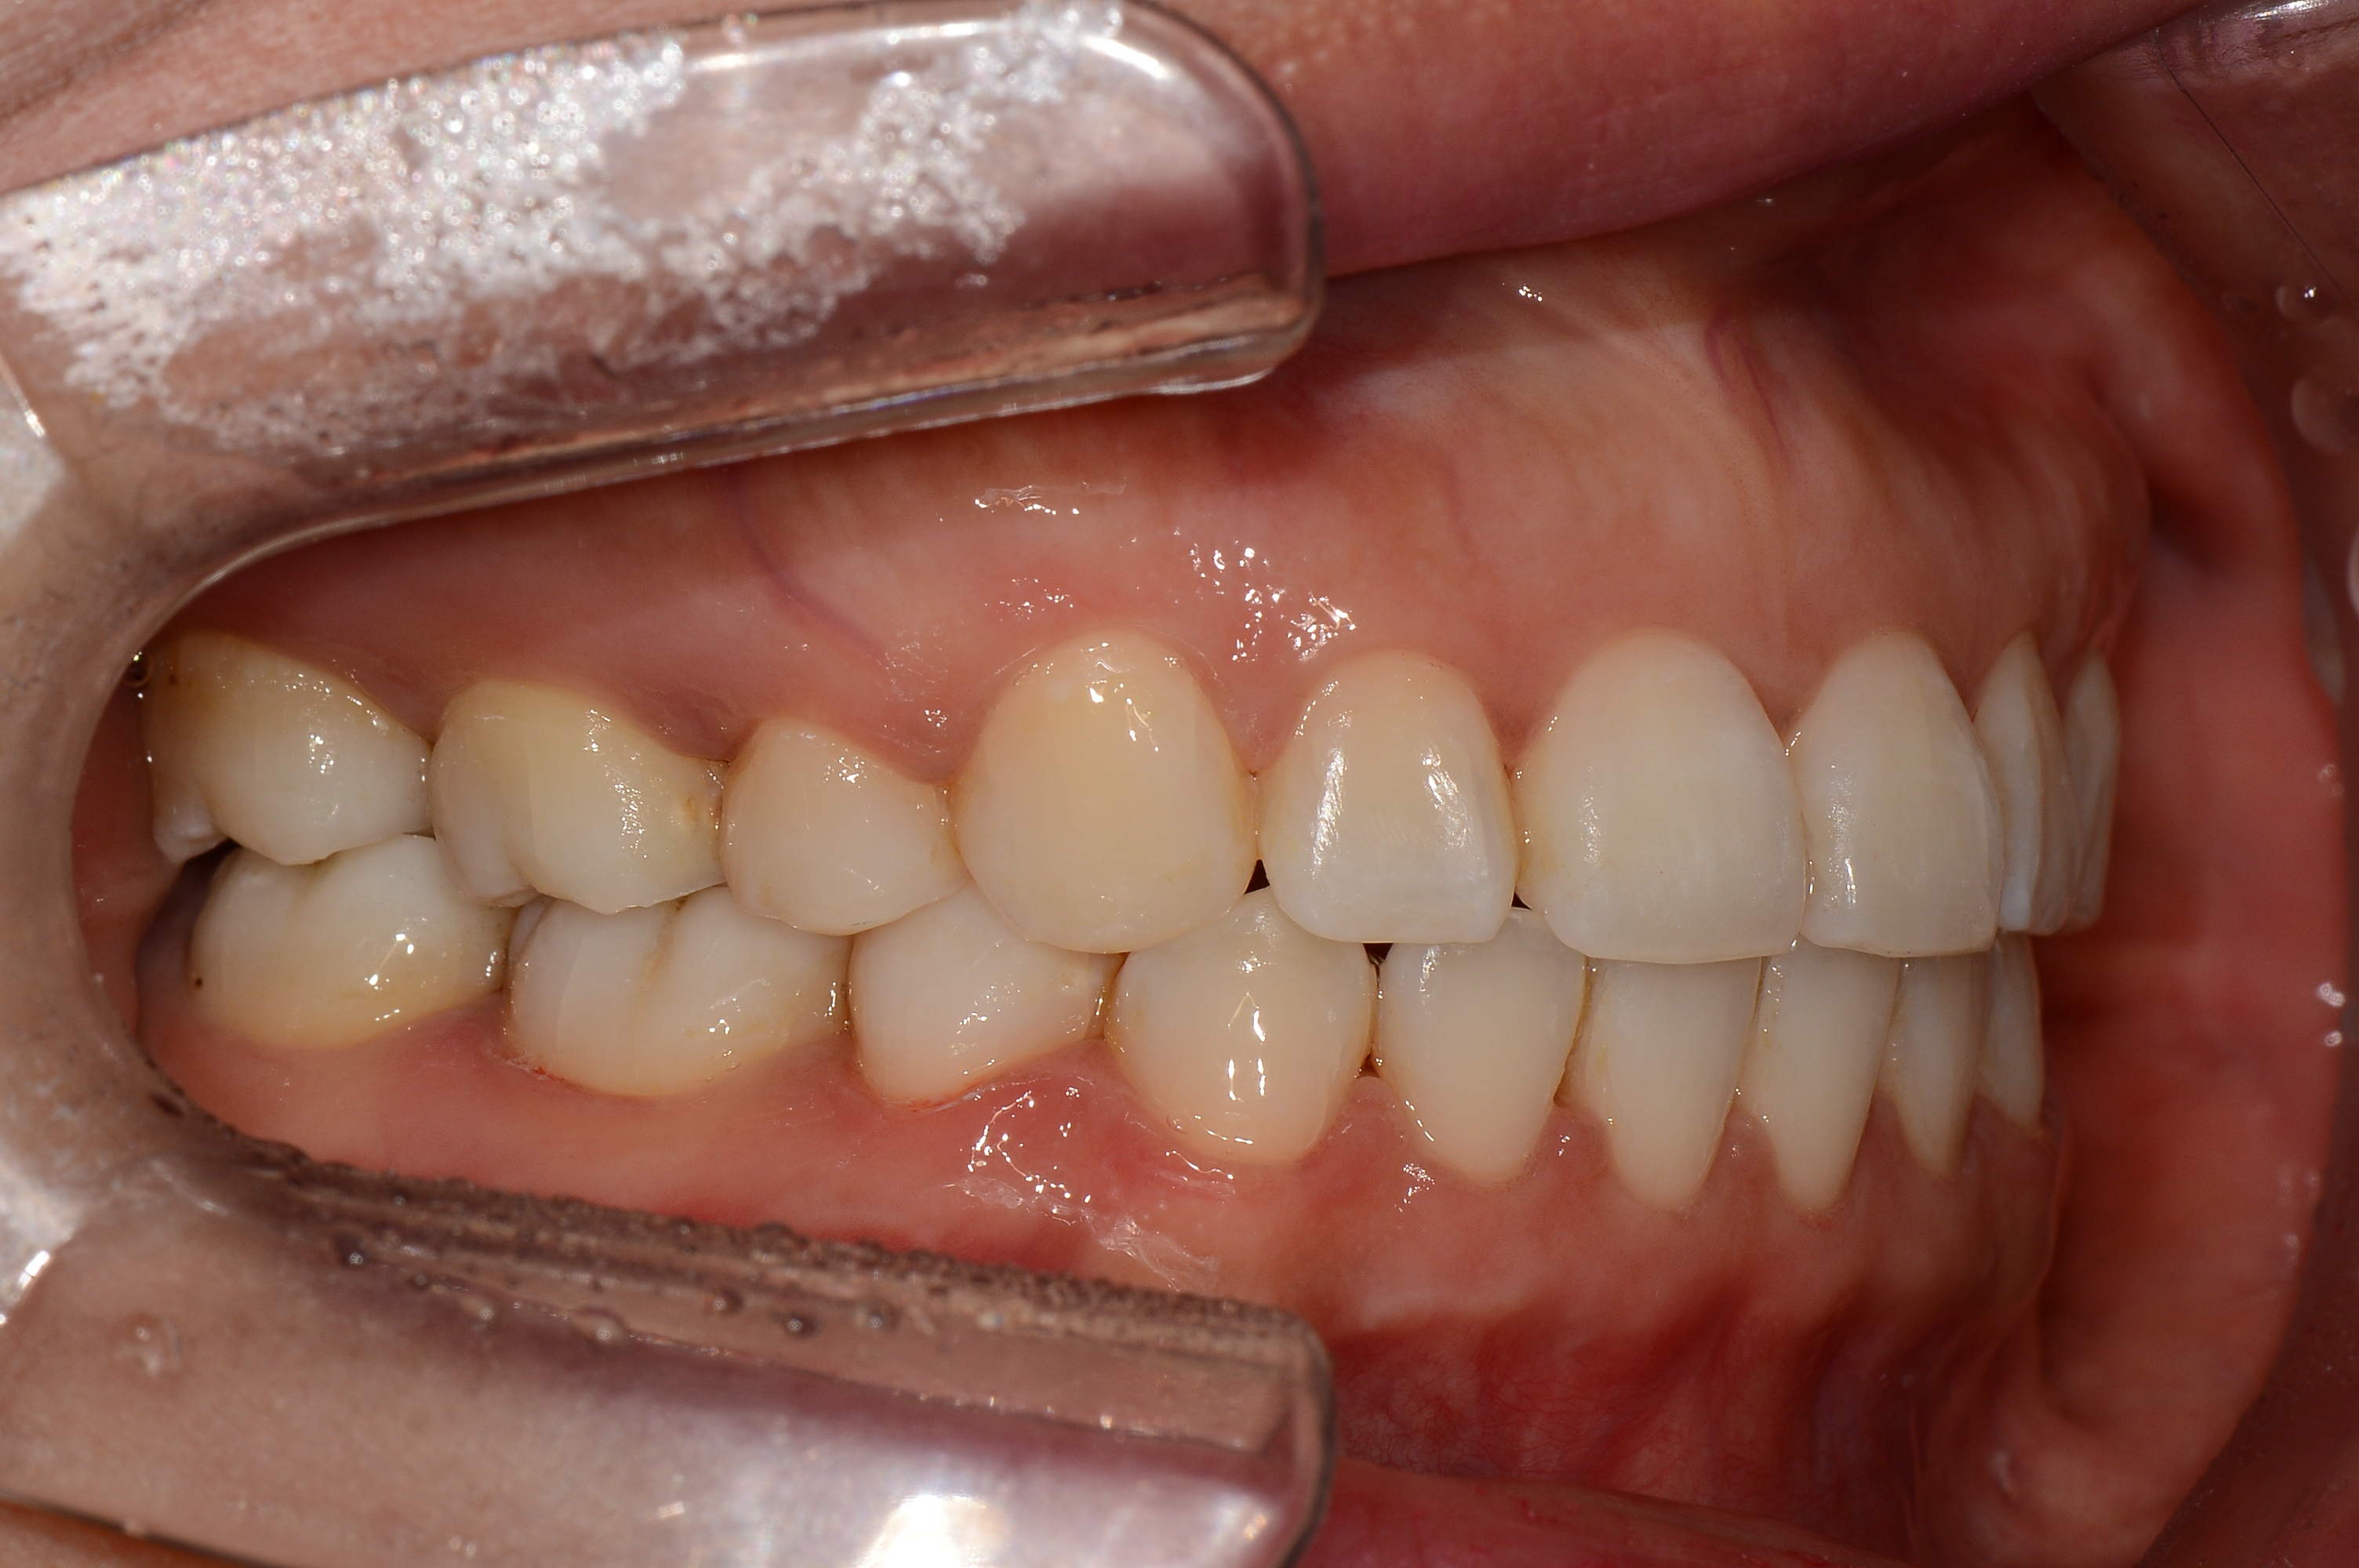

치료 전 사진입니다.